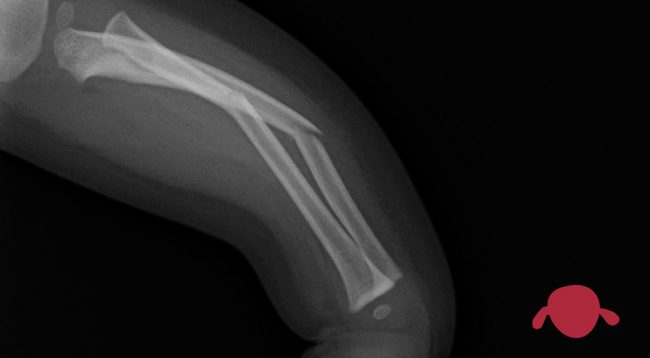

Una curiosidad saber el peso de una escayola. Pero si tu hijo tiene un problema nutricional y controlas bien el peso, es importante saber el cambio de peso que es culpa de la escayola. La escayola de la foto corresponde un “botín” de yeso, es decir por debajo de la rodilla, de un…